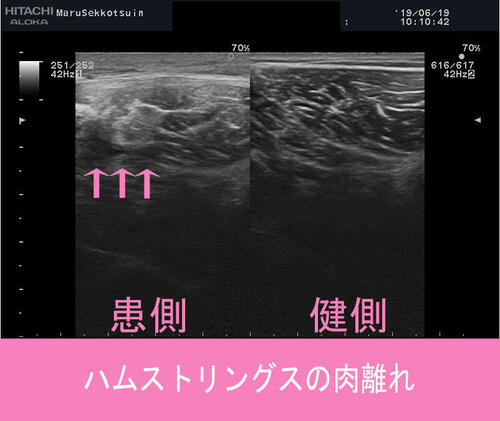

今回もしっかりと問診、触診、視診を行い、確認の為にエコー検査。

ハムストリングスの肉離れ.jpg

結果、肉ばなれの好発部位「大腿二頭筋の肉離れ」